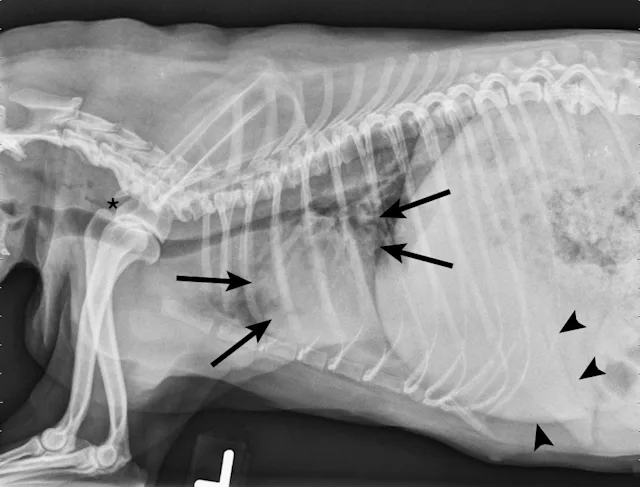

On examination, the dog was panting with expiratory effort and crackles auscultated diffusely. She exhibited an occasional goose-honking cough and retch. Her body temperature was normal. Radiography (Figures 1 and 2), fluoroscopy (Figure 3), and bronchoscopy (Figures 4 and 5) were performed.

FIGURE 1

Left lateral radiograph showing dynamic collapse of the intrathoracic trachea from the level of the thoracic inlet to the mainstem bronchi. A small amount of esophageal gas is observed (asterisk), and the lungs are hypoinflated, which is likely secondary to increased respiratory effort. Mild, generalized cardiomegaly and hepatomegaly are also evident in the thorax (arrows) and abdomen (arrowheads), respectively.